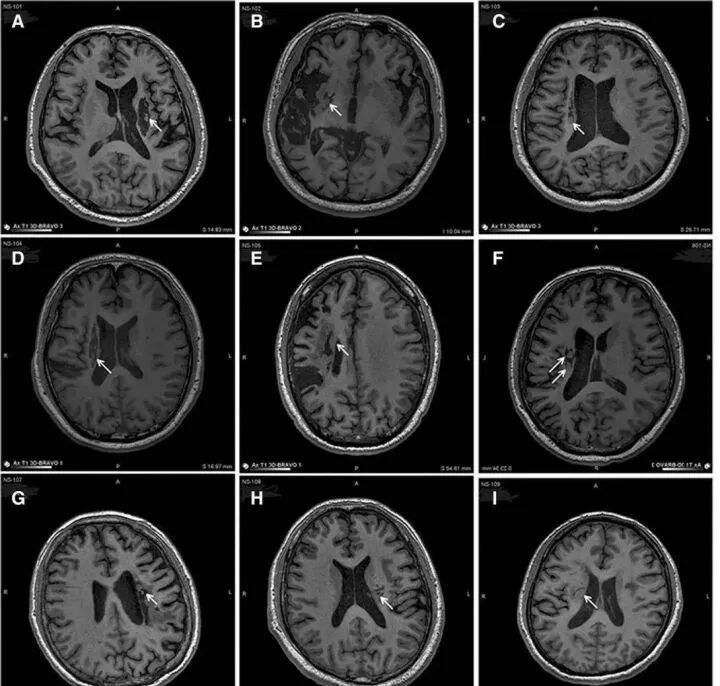

2019年,《干细胞转化医学》(Stem Cells Translational Medicine)杂志上公布,干细胞回输有助于脑卒中偏瘫患者运动功能的恢复。9名年龄在30至65岁之间的偏瘫患者参与了这项临床研究,他们在中风后5-24个月接受干细胞脑内回输,干细胞被回输至脑内梗塞灶附近。影像学研究的结果表明,干细胞输入区出现了新的神经组织,这也证明了干细胞干预偏瘫性脑卒中拥有一定的临床益处

△9例患者的影像学显示病变区域的组织都发生了明显变化

回输到脑内梗塞病灶的干细胞,通过分化为神经系统的各类细胞、分泌营养因子,促进神经和血管再生,修复受损的血-脑脊液屏障,减轻炎性反应等促进脑梗死动物的神经功能恢复,让9例临床患者偏瘫的症状得到了明显改善。